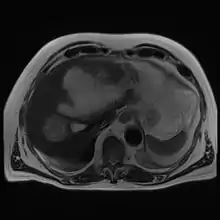

Amoebic liver abscess

A amoebic liver abscess is a type of liver abscess caused by amebiasis.[1] It is the involvement of liver tissue by trophozoites of the organism Entamoeba histolytica and of its abscess due to necrosis.

| Gross pathology of liver containing amoebic abscess | |